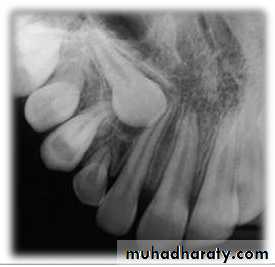

645. Presence of Root Resorption of the Adjacent

IncisorThe presence or absence of root resorption of the

adjacent upper incisor was recorded as judgedfrom examination of the OPG, although, a further

50 per cent of patients may have bucco-lingual root

resorption that is not diagnosed by routine

radiography (Ericson and Kurol, 1987).

4. Canine Overlap of the Adjacent Incisor Root

Grade 1: No horizontal overlap.Grade 2: Less than half the root width.

Grade 3: More than half, but lessthan the whole root width.

Grade 4: Complete overlap of rootwidth or more.